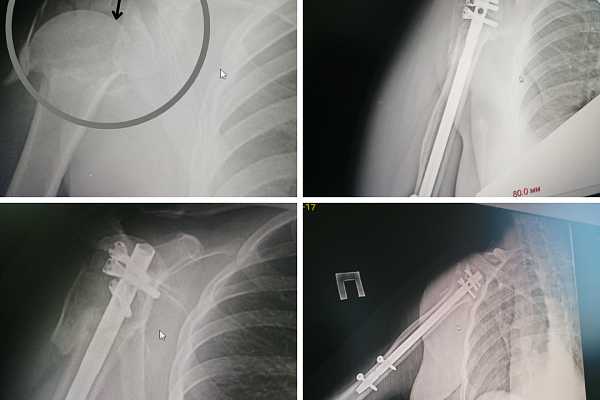

Одна из них серьёзно травмировала головку плеча. Мелкооскольчатый перелом стал настоящей катастрофой для сустава. Дома помощь ограничилась гипсовой иммобилизацией. Решив обратиться к сургутским травматологам, женщина преодолела не одну тысячу километров. При таких разрушениях, когда вероятность сращения незначительная, в качестве лечения, как правило, рассматривают эндопротезирование. Но, в отличие от коленных или тазобедренных суставов, установка и дальнейшая эксплуатация искусственного плечевого сустава сопровождается целым рядом сложностей и рисков. К тому же, нельзя было не принять во внимание возраст пациентки. Женщине чуть больше 40-ка, поэтому, хоть и в отдалённом будущем, но необходимость замены протеза всё-таки назреет. А перспектив повторного (ревизионного) эндопротезирования плечевого сустава немного.

– Было принципиально важно сохранить молодой женщине свой рабочий сустав. Оценив характер повреждений и современные возможности, мы выбрали метод интрамедуллярного остеосинтеза. Это внутрикостный вид оперативного лечения: в костномозговую полость погружается многофункциональный штифт-фиксатор, а затем винтами закрепляются образовавшиеся при переломе осколки. Технически операция довольно сложная, она требует чёткого предварительного планирования и тщательного обследования пациента. Однако травматичность такого вмешательства минимальная, конечность можно нагружать уже через несколько дней. Сейчас пациентка разрабатывает руку на занятиях ЛФК, функции конечности вернулись на 50%, перелом консолидировался, болевой синдром регрессировал, – говорит заведующий ортопедо-травматологическим отделением №4 Евгений Бойко.

В Сургутской травмбольнице широко применяется и другой вид остеосинтеза – накостный, когда отломки собираются пластинами. В данном случае специалисты посчитали его слишком травматичным методом лечения. Зато другой пациентке он подошёл идеально. Тоже не являясь югорчанкой, пожилая женщина доверилась именно нашим врачам. Перелом плечевой кости – самый обычный. Вот только условия для его сращения своевременно обеспечены не были. В итоге под силой тяжести костные отломки разошлись на большое расстояние друг от друга, и лишившаяся опоры рука повисла на мягких тканях, как плеть.